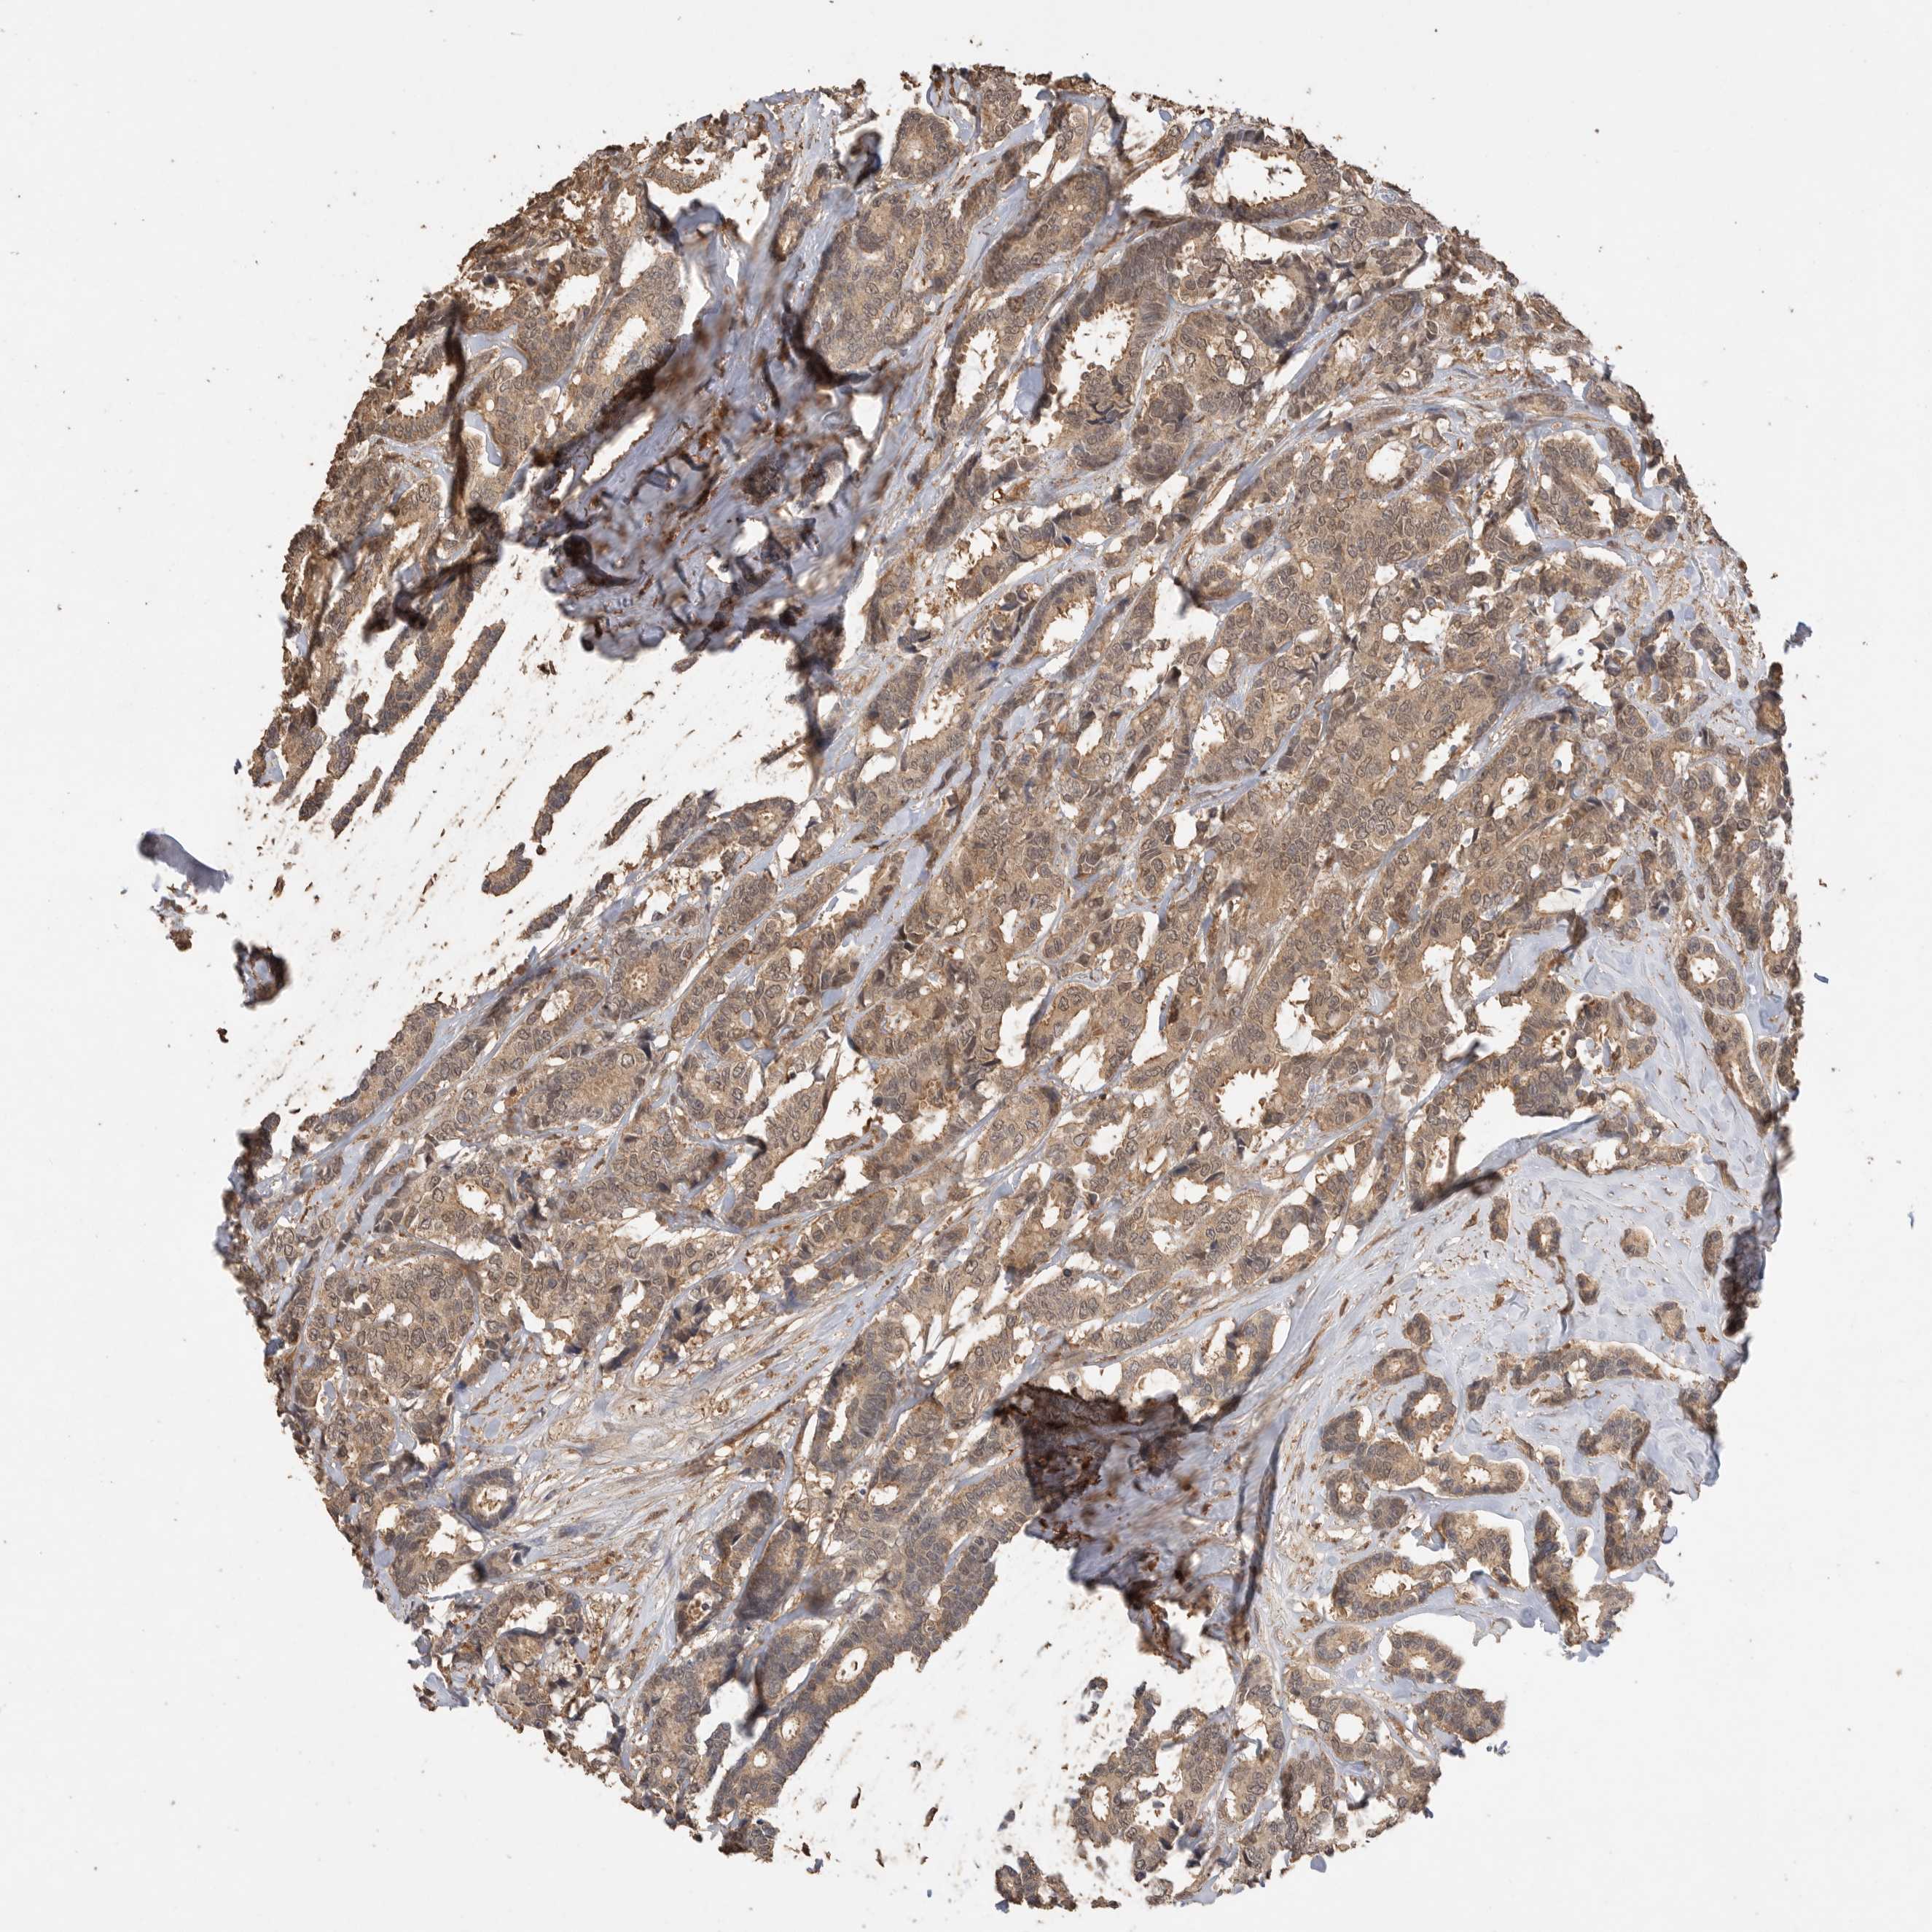

BRCA TCGA BRCA VALIDATION PROTEIN EXPRESSION